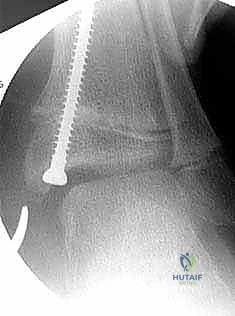

Implant Selection and Guide Wire Placement

A two-hole tension band plate is selected. The size of the plate is determined by the anatomy of the patient; the plate must be long enough to span the physis without the screws violating the physeal cartilage, yet short enough to avoid impinging on the medial collateral (deltoid) ligament insertion or the tibiotalar joint capsule.

The plate is positioned over the medial distal tibia, centered exactly over the physis in both the AP and lateral planes. A central guide hole in the plate (if present) can be placed over the previously inserted physeal marker needle.

Once the plate is optimally positioned, the epiphyseal guide wire is inserted first. The trajectory of this wire is critical. On the AP view, it must be parallel to the joint line. On the lateral view, it must be directed strictly in the coronal plane, aiming for the center of the epiphysis. It must not violate the articular surface of the tibiotalar joint.

Subsequently, the metaphyseal guide wire is inserted. This wire should be parallel to the epiphyseal wire to ensure the plate sits flush against the bone. Fluoroscopy in both orthogonal planes is mandatory at this stage to confirm that the wires are extra-articular, do not cross the physis, and are centrally located within the bone.

Drilling and Hardware Insertion

With the guide wires in perfect position, a cannulated drill is used to breach the near cortex. Care is taken not to plunge deeply, as the cancellous bone of the pediatric metaphysis and epiphysis is soft and easily accepts the self-tapping screws.

Cannulated, partially threaded or fully threaded screws (typically 4.0 mm or 4.5 mm in diameter, depending on the system) are advanced over the guide wires. The epiphyseal screw is usually placed first. The length of the screws should be sufficient to engage the dense cancellous bone centrally but must not breach the far (lateral) cortex, which could tether the lateral physis. Typically, 16 mm to 24 mm screws are appropriate.

As the screws are tightened, the plate should compress flush against the medial cortex. The surgeon must ensure that the screws are not over-tightened to the point of stripping the soft metaphyseal bone.

Final Evaluation and Closure

Final AP and lateral fluoroscopic images are obtained to document the exact placement of the hardware. The screws should be divergent or parallel, spanning the open physis, with the plate resting flat against the bone.